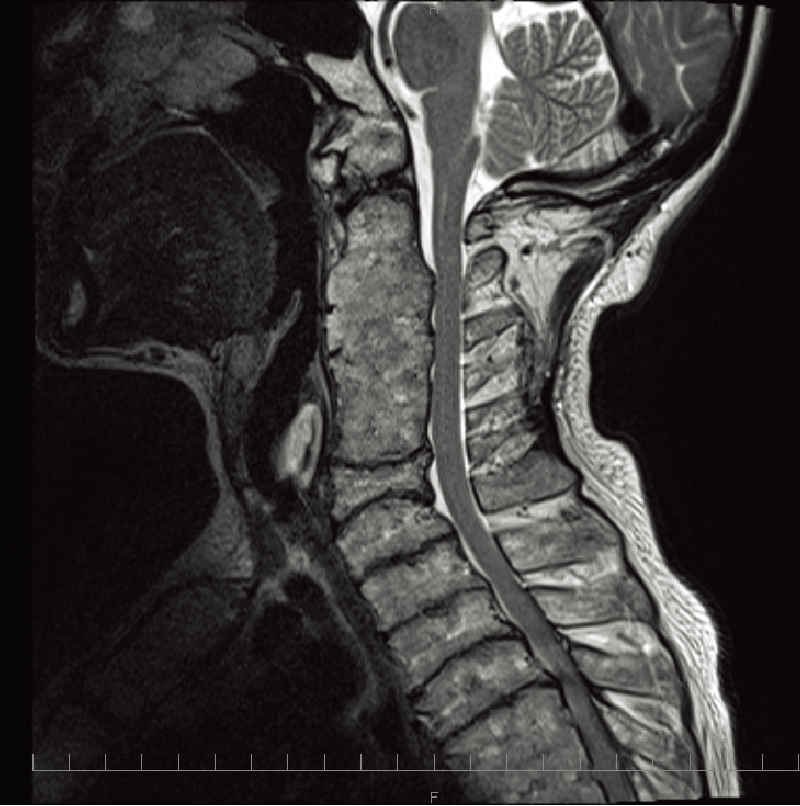

A、B. 頚髄、腰髄MRIT2強調矢状断像(35歳、女):前後径が増大した扁平椎と脊柱管狭窄を認める。